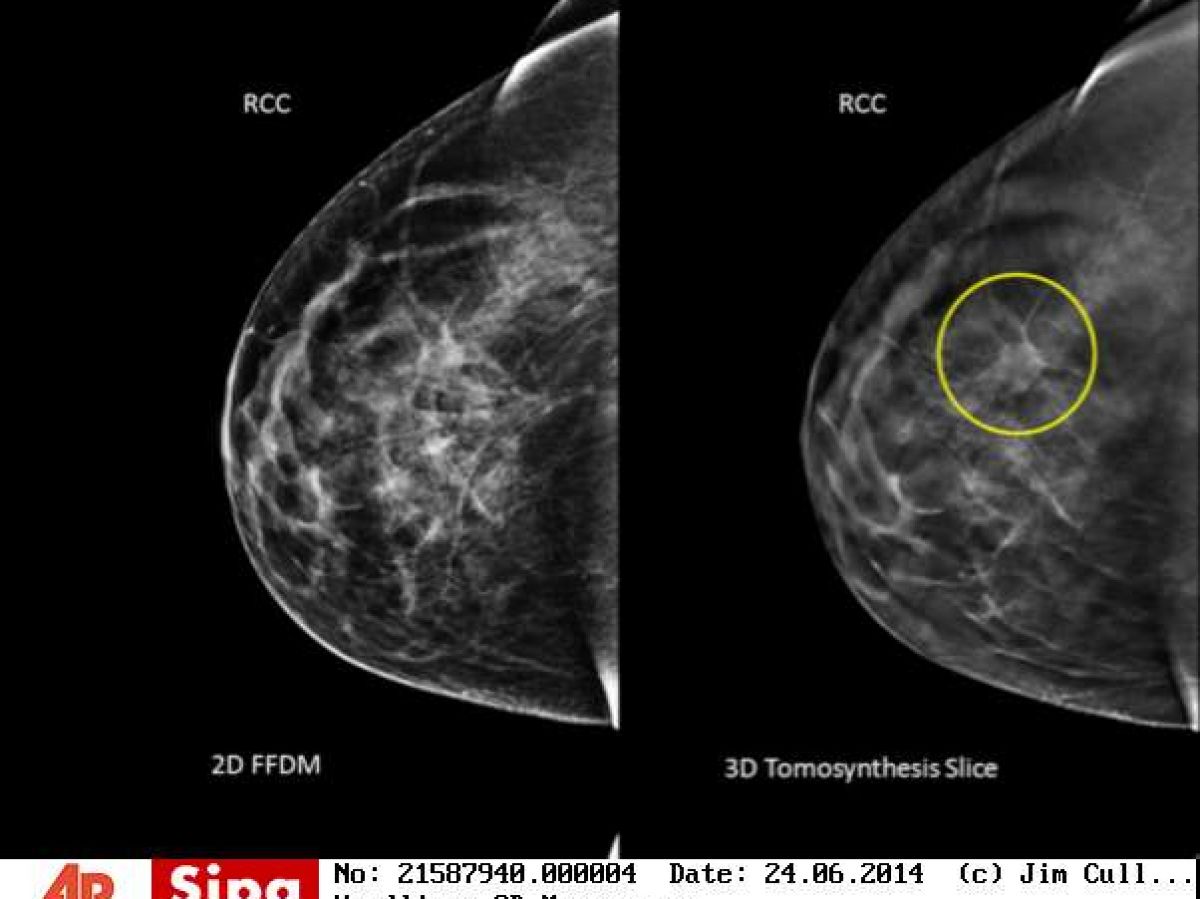

- La mammographie ;